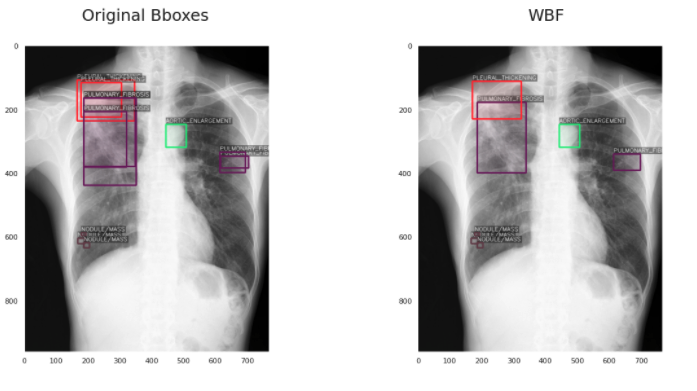

给大家介绍一下背景,这个比赛是关于用x光检查肺部疾病的。你的模型必须能够区分14种不同的疾病,并且对每种疾病预测出疾病所在的边界框。这变得更加困难,因为每个图像可能有不止一种疾病(因此你必须预测多个不同的边界框)。

第一个问题是,这些疾病是由多个不同的放射科医生标记的,对于同一种异常可能有多个不同的边界框。所以我们必须过滤这些(或者在本例中“融合”它们),以避免混淆我们的模型。

第二个问题是一些密集疾病区域包含多个标签,这意味着一个小的包围框可以有多个疾病标签。如果我们使用像NMS这样的东西,会很困难,因为我们是根据IoU过滤框。因此,像NMS这样的方法很可能会删除有用的框。

我将讨论每一种技术,包括使用该技术之前和之后的边界框的可视化。